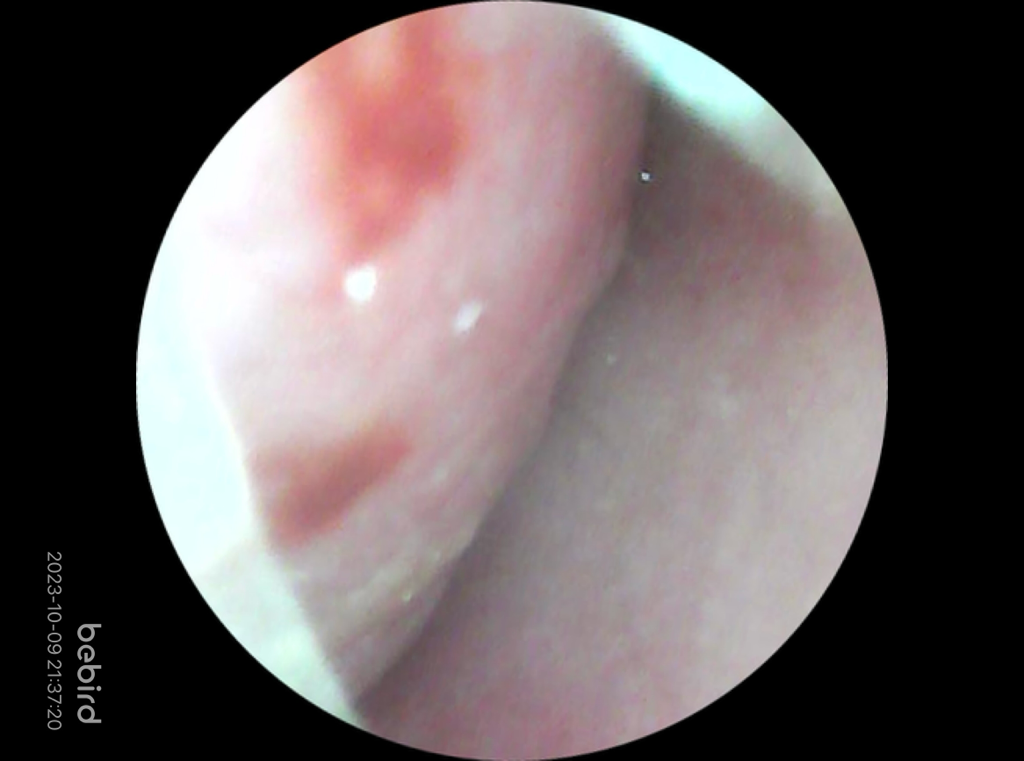

집에 내시경 기능 비슷한 기기가 있어서 찍어봤는데

위쪽이 왼쪽코, 아래쪽이 오른쪽 코 사진이에요

• 2번 째 사진

비강 내 점막의 부종이 관찰되며, 혈관운동성 비염의 경우 치료는 원인 회피 및 증상 호전에 초점을 맞추게 되며, 근본적인 치료는 어렵습니다. 강한 향기, 음주, 매운 음식, 온습도 변화 등 증상을 유발할 수 있는 원인들을 회피하는 것이 최선입니다. 따라서 증상이 심하지 않다면 가정에서 지켜보시고, 증상이 불편한 경우 경구 약물 또는 비강내 스테로이드 스프레이 등을 처방받아 사용해 볼 수 있겠습니다.